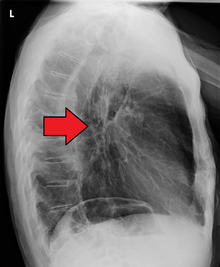

Radiotherapy is given before, during, or after chemotherapy or surgery, and sometimes on its own to control symptoms. In patients with localised disease but contraindications to surgery, "radical radiotherapy" may be used with curative intent.

Internal radiotherapy for esophageal cancer